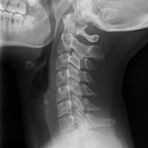

Konventionelles Röntgen

Der Begriff Röntgen, oder auch Röntgendiagnostik bezeichnet ein Verfahren in der Radiologie, bei dem von einer Röntgenröhre elektromagnetische Wellen (Röntgenstrahlen) durch die zu untersuchende Körperregion des Patienten gesendet werden. Je nach Dichte der Gewebeart des Körpers (z.B. Knochen oder Lunge) werden die Röntgenstrahlen im Körper unterschiedlich stark abgeschwächt. Ein digitaler Detektor empfängt dann die Röntgenstrahlen, die in abgeschwächter Form den Körper wieder verlassen haben. Daraus wird das Röntgenbild erzeugt.

Die zu untersuchenden Anteile des Körpers werden meistens

in 2 unterschiedlichen Projektionsebenen dargestellt.

In einigen Körperregionen sind spezielle Zielaufnahmen notwendig.

Die Röntgenuntersuchung ist weiterhin eine unverzichtbare Basisdiagnostik. Viele Fragen können in der medizinischen Diagnostik mit einer konventionellen Röntgenaufnahme geklärt werden.